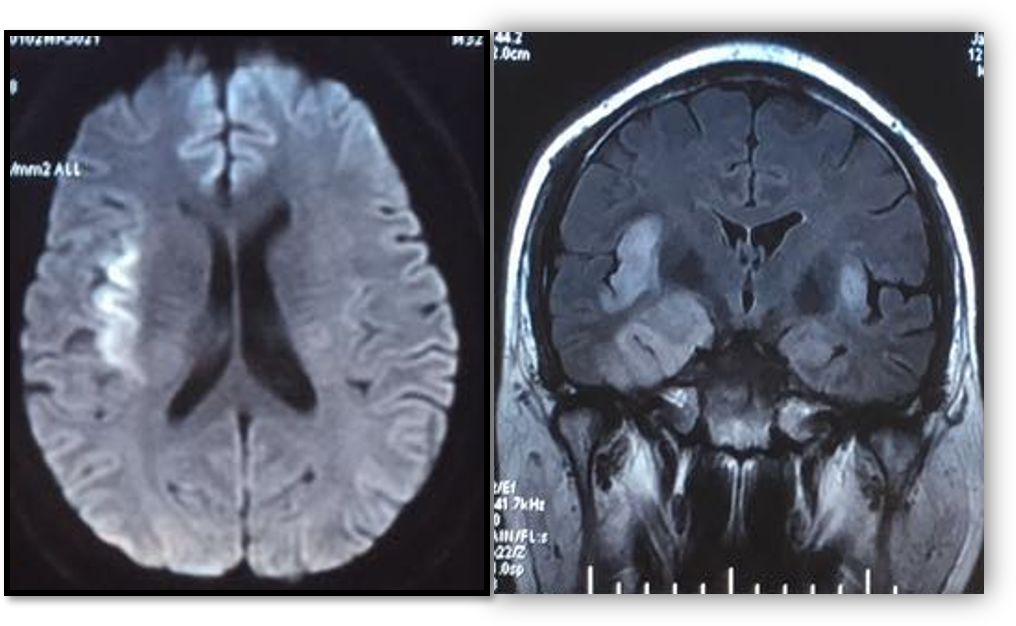

影像表现如下:

头颅MRI可见双侧颞叶、岛叶、海马多发片状异常信号,右侧为著,FLAIR呈明显高信号,DWI轻度弥散受限。基底节层面矢状位DWI及冠状位FLAIR隐约可见“刀切征”。结合发热、精神改变病史,高度提示单纯疱疹病毒脑炎。后完善自身免疫抗体(NMDA、LGI1、CASPR2、GABA-B):均为阴性。

病原体高通量测序提示:人单纯疱疹病毒。

诊断: 单纯疱疹病毒脑炎。